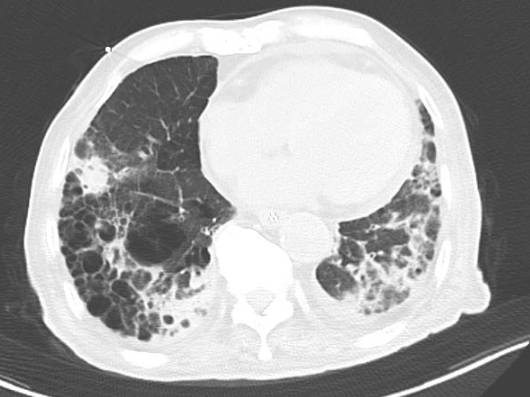

??近日,潍坊市人民医院老年医学科接诊一例高龄患者,因饮食不佳5天来诊,无发热,偶有咳嗽咳痰,无恶心呕吐,无胸痛,在外未予治疗。双肺可闻及湿性啰音,余无明显异常。完善相关辅助检查,血常规及肺部CT结果提示肺炎。

??图2 肺部CT